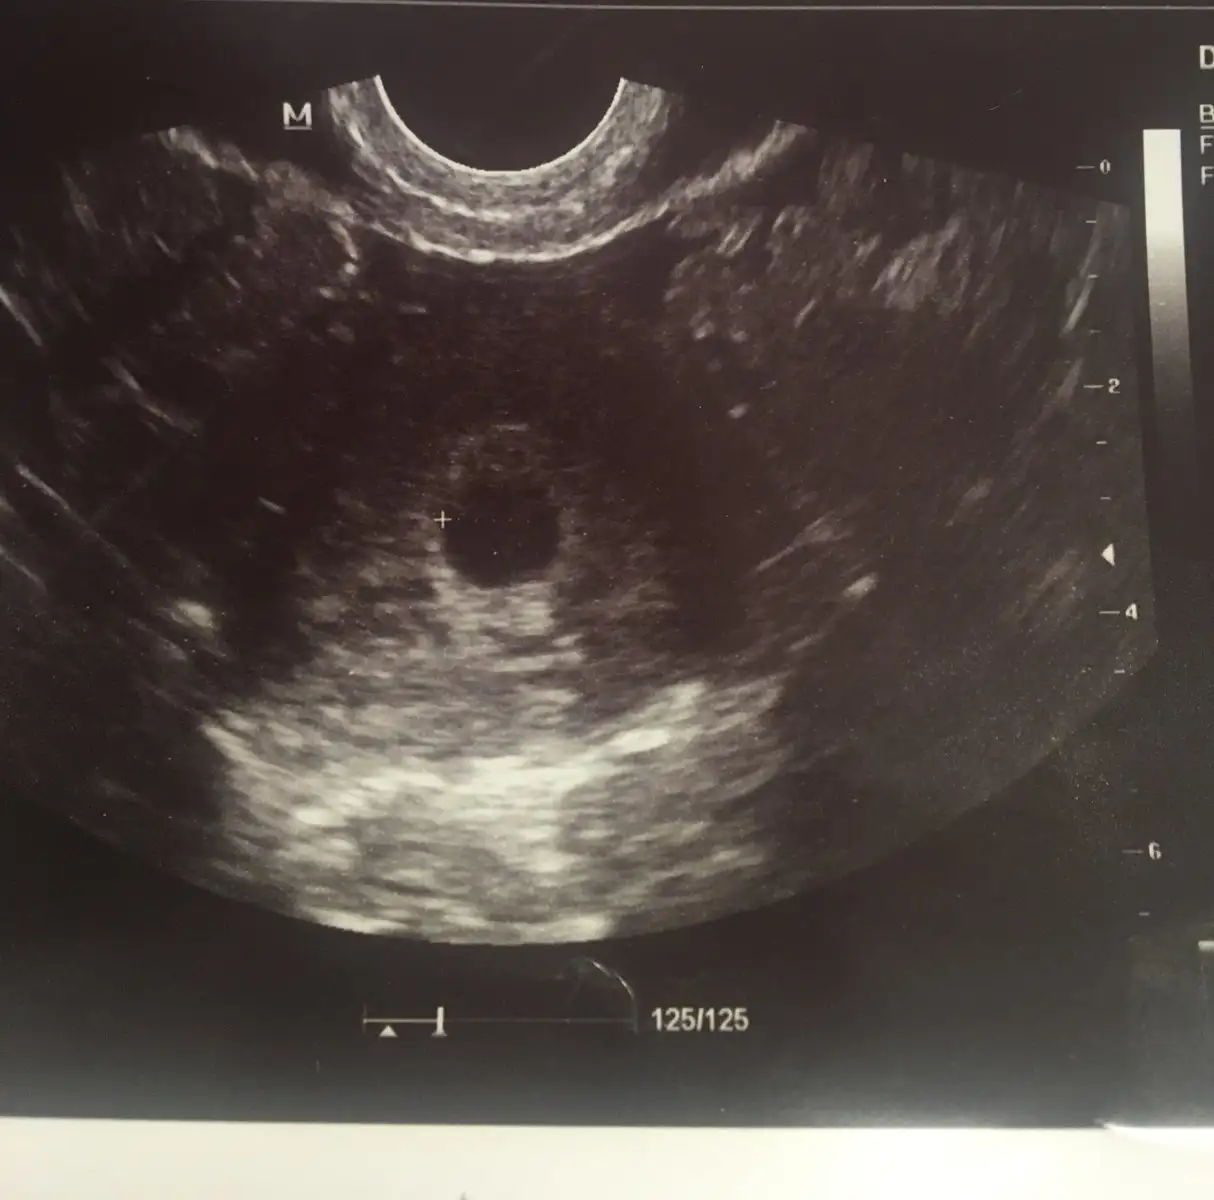

Ben kız diyorum :)Kızlar bugunden sıcak sıcak 8 haftalık fotoğrafımız bizede bir yorum teyzeleri

Kiz diyorumTahmin hissiyat sizce nedir hanimlar.

Karından ultrason sağda olunca kız yazmışlar genelde. Amaç eğlenmek :)Yorumlardan anladığım erkek bebek. Tam bilmiyorum bende ama böyle olunca erkek yazıyorlar

Kızlar bir yorum alabilir miyiz?

Kız gibi tatlım